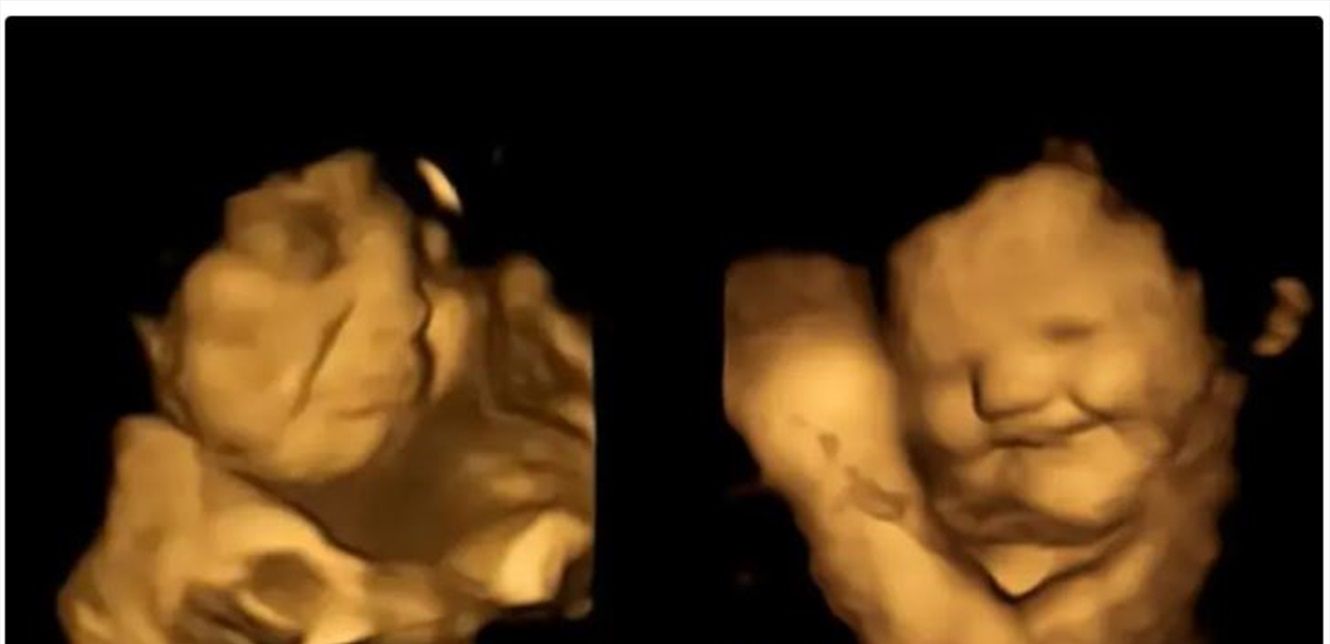

تمكن علماء، بعد رصدهم وجوه الأجنة بموجات فوق صوتية، من التعرف إلى الحالة النفسية للأجنة وهم في أرحام أمهاتهم يتناولون الطعام لأول مرة، ووجدوا أن الجنين يبتسم حين يتذوق الجزر ويعبس تكشيرا عندما يتناول اللفت، بحسب ما اتضح من تجارب خضعت لها 100 امرأة حامل، وابتلعت كل منهن كبسولة تحتوي على 400 ملليغرام من مسحوق الجزر أو الكرنب الملفوفي.

وبحسب ما بينت النتائج، فإن من تذوقوا نكهة الجزر اللطيفة أظهروا باستمرار استجابات أكثر "لوجه ضحوك" بعكس من تذوقوا الكرنب الملفوفي المر، حيث ظهر كل منهم بوجه عابس، لذلك ورد بالدراسة أن الكراهية الغريزية للطعم المر "هي منطقية من وجهة نظر تطورية، وهذا ما ساعد أسلافنا على تجنب السموم" لأن طعم معظمها منفر كرائحتها.